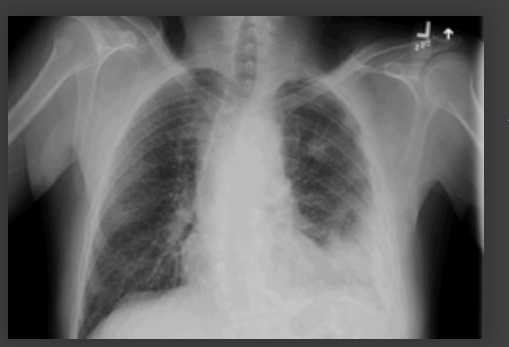

Cavitação — A TC ajuda a identificar diagnósticos alternativos, como tuberculose, câncer de pulmão, infarto pulmonar, embolia pulmonar séptica, bolha infectada, abscesso pulmonar[Figure caption and citation for the preceding image starts]: Radiografia de tórax mostrando pneumonia cavitando no lobo superior esquerdoDa coleção do Dr. Jonathan Bennett. Usado com permissão [Citation ends].